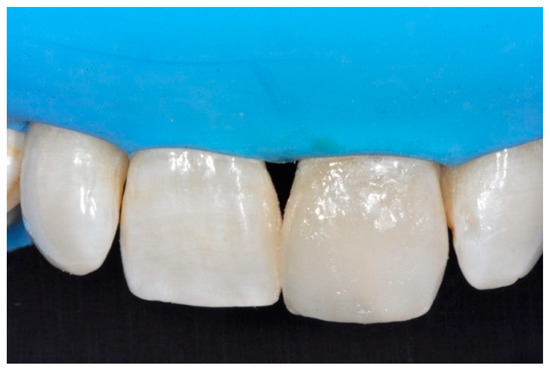

Figure 37.

Final result after finishing and polishing. Reprinted from Restauri diretti nei settori anteriori, G. Paolone, S. Scolavino, © 2021, with permission from Quintessence Publishing Italy.